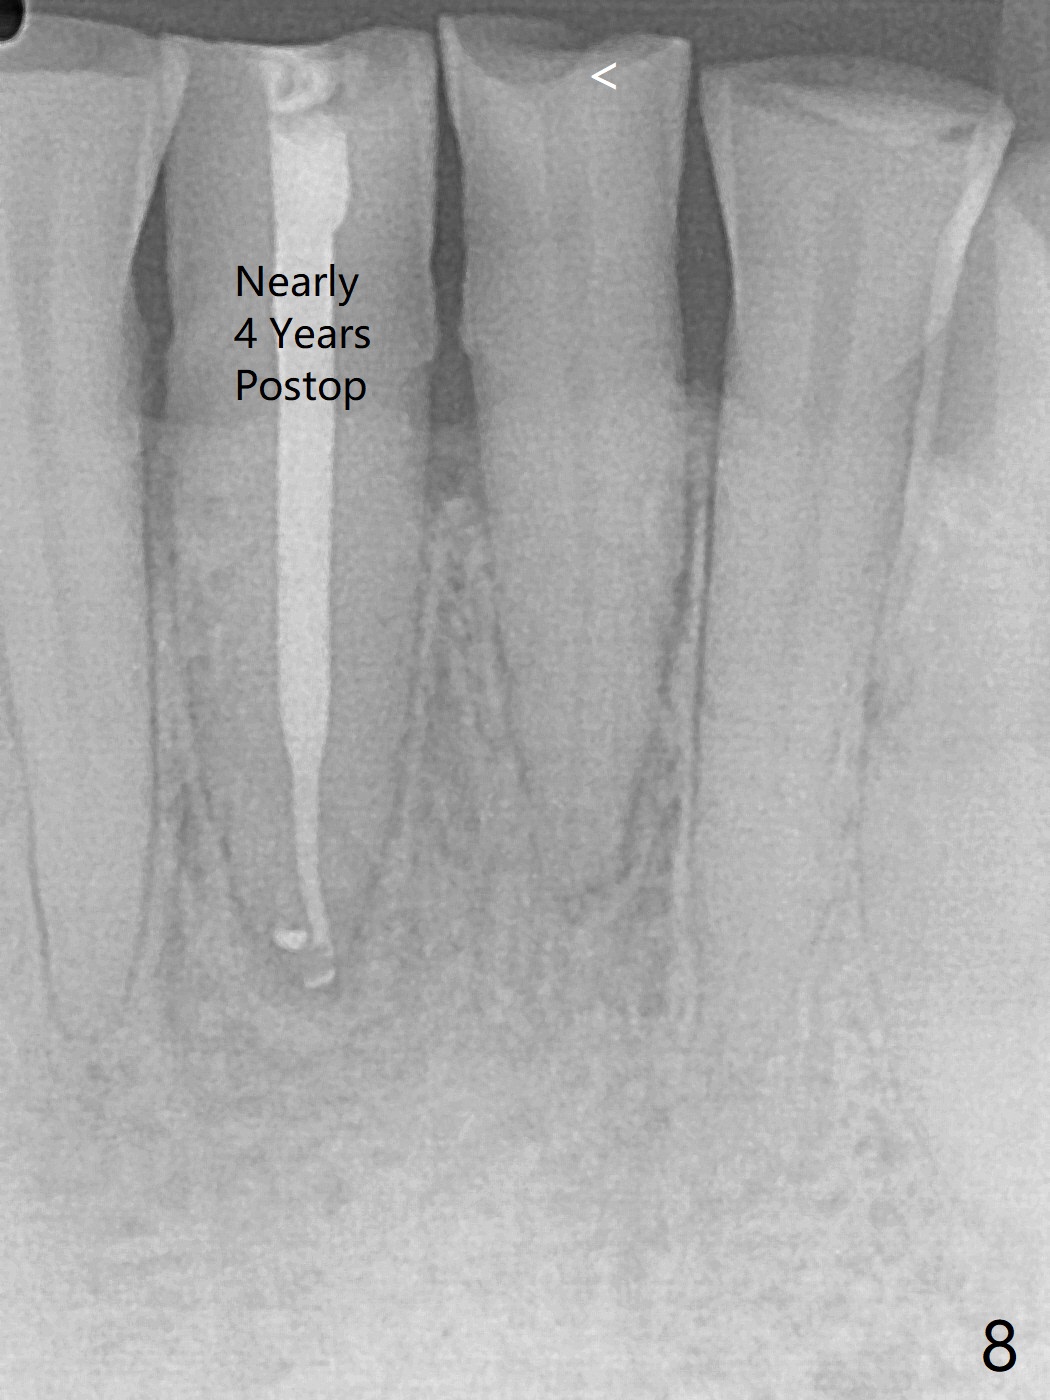

A 45-year-old man has had a chronic fistula associated with the tooth #25 (Fig.1). There is purulent discharge sometimes. After debridement with hand files #10-20 and rotary one 30/06, a master cone 30/.06 is inserted incompletely (Fig.2). After rotary files 30/.08 at 16.0 mm and 30/.10 at 15.0 mm and hand files 10-20 at 17 mm, the master cone is apparently inserted to the WL. With application of Endo Sequence Sealer (syringe), the master cone is reinserted (Fig.3). When the rubber dam is removed, the sealer is found to have expelled from the fistula. With an endo curette (Fig.5), the sealer is removed from the deepest portion of the sinus tract (apex of the tooth). What do you want to know the outcome of the supplementary surgical maneuver? The sealer is gone (Fig.6). The immediately supplementary treatment avoids a separate apicoectomy. No fistula is noted <2 weeks postop (Fig.7). The attrition is due to #8 and 9 veneers, fabricated 8 years earlier. The tooth #24 is symptomatic with loss of incisal composite nearly 4 years postop (Fig.8 <). After 30/.04 gutta percha (GP) try in (Fig.9), RCT is finished without accessory GP (Fig.10).